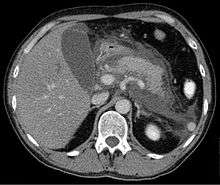

- Acute pancreatitis is diagnosed clinically but requires CT evaluation to differentiate mild acute pancreatitis from severe necrotic pancreatitis. Experienced clinicians were able to detect severe pancreatitis in approximately 34-39% of patients who later had imaging confirmed severe necrotic pancreatitis. Blood studies are used to identify organ failure, offer prognostic information, determine if fluid resuscitation is adequate, and if antibiotics are indicated.

- Imaging – A triple phase abdominal CT and abdominal ultrasound are together considered the gold standard for the evaluation of acute pancreatitis. Other modalities including the abdominal x-ray lack sensitivity and are not recommended. An important caveat is that imaging during the first 12 hours may be falsely reassuring as the inflammatory and necrotic process usually requires 48 hours to fully manifest.

Computed tomography

Regarding the need for computed tomography, practice guidelines state:

CT is an important common initial assessment tool for acute pancreatitis. Imaging is indicated during the initial presentation if:

- the diagnosis of acute pancreatitis is uncertain

- there is abdominal distension and tenderness, fever >102, or leukocytosis

- there is a Ranson score > 3 or APACHE score > 8

- there is no improvement after 72 hours of conservative medical therapy

- there has been an acute change in status: fever, pain, or shock

CT is recommended as a delayed assessment tool in the following situations:

- acute change in status

- to determine therapeutic response after surgery or interventional radiologic procedure

- before discharge in patients with severe acute pancreatitis

CT abdomen should not be performed before the first 12 hours of onset of symptoms as early CT (<12 hours) may result in equivocal or normal findings.

CT Findings can be classified into the following categories for easy recall :

- Intrapancreatic – diffuse or segmental enlargement, edema, gas bubbles, pancreatic pseudocysts and phlegmons/abscesses (which present 4 to 6 wks after initial onset)

- Peripancreatic / extrapancreatic – irregular pancreatic outline, obliterated peripancreatic fat, retroperitoneal edema, fluid in the lessar sac, fluid in the left anterior pararenal space

- Locoregional – Gerota's fascia sign (thickening of inflamed Gerota's fascia, which becomes visible), pancreatic ascites, pleural effusion (seen on basal cuts of the pleural cavity), adynamic ileus, etc.